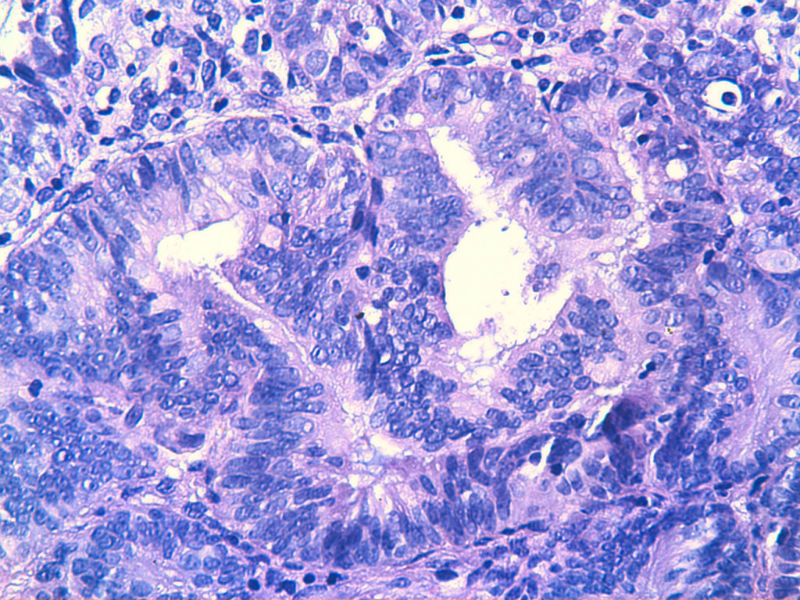

子宫内膜EIN?

图13是做为正常对照的,图7、8、9、12显示的核大小不一,空泡状,形状不规则。女,48岁,宫血半年

复杂性非典型增生

复杂伴非典

子宫内膜呈增生期改变伴局灶区域腺体密集核异性够EIN.

复杂性增生伴非典型性。